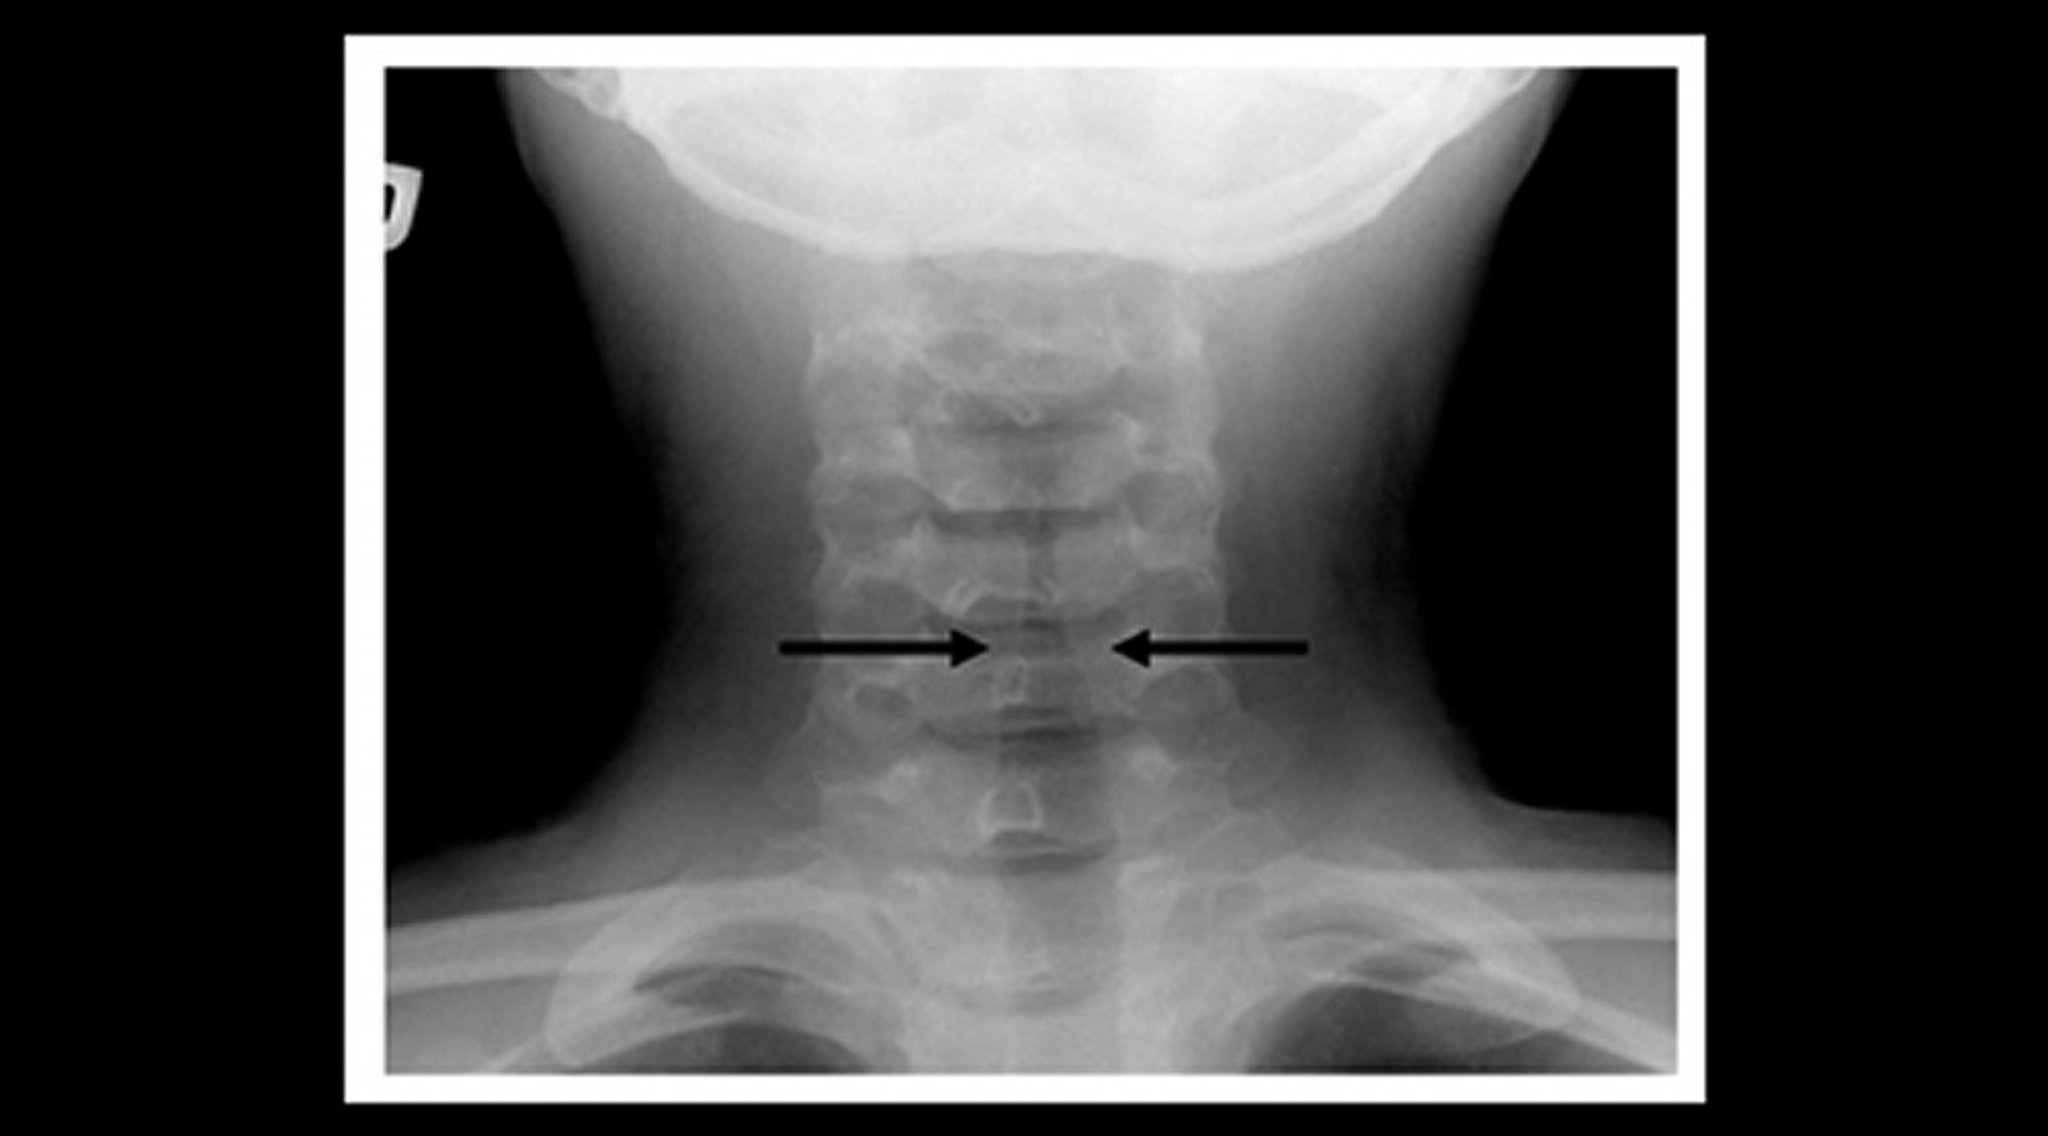

Radiograph of a Child With Croup (Coronal View)

Soft-tissue neck radiograph of a child with croup shows gradual narrowing of the subglottic tracheal lumen and its air shadow (steeple sign—arrows) and dilation of the pharyngeal air spaces.

Image courtesy of John McBride, MD.